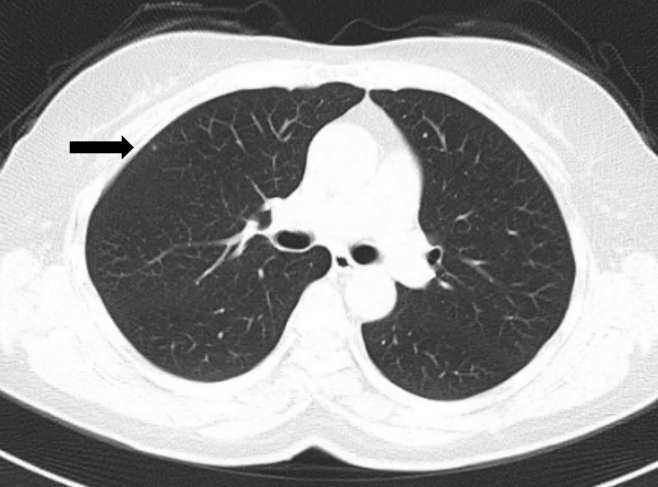

右肺上叶微小结节

上图中用黑色箭头指出来的这一个小点就是肺内的微小结节。为什么要这么在意结节的大小呢?北京协和医院呼吸与危重症医学科副主任医师徐燕医生表示,因为肺内结节越小,它可能是恶性的概率就越低;而肺内结节越大,那么它是恶性的概率就会相应的增高。

大部分<5mm的结节是恶性的可能性小于1%,基本上都是良性的。所以如果CT结果显示为2mm、3mm的微小结节,基本上不用太紧张。当肺内的病灶超过2cm的时候,它的恶性程度就会显著增高,超过3cm时甚至有一半的可能性可能是一个恶性的病变。